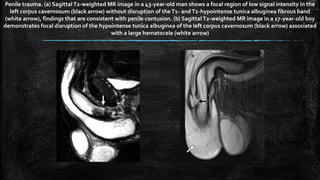

Penile trauma. (a) SagittalT2-weighted MR image in a 43-year-old man shows a focal region of low signal intensity in the

left corpus cavernosum (black arrow) without disruption of theT1- andT2-hypointense tunica albuginea fibrous band

(white arrow), findings that are consistent with penile contusion. (b) SagittalT2-weighted MR image in a 17-year-old boy

demonstrates focal disruption of the hypointense tunica albuginea of the left corpus cavernosum (black arrow) associated

with a large hematocele (white arrow)